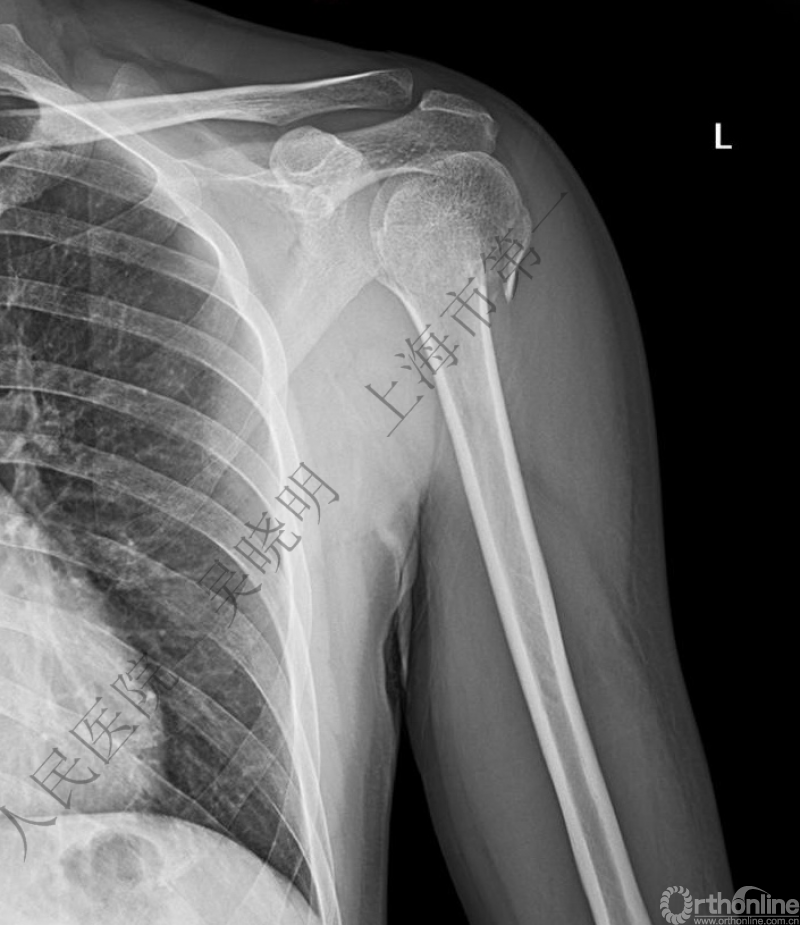

下图考虑为孤立性的大结节骨折?

看完片子,你会发现高质量的平片甚至3D CT也难以发现

X线看不清骨折线,三维CT也看不清